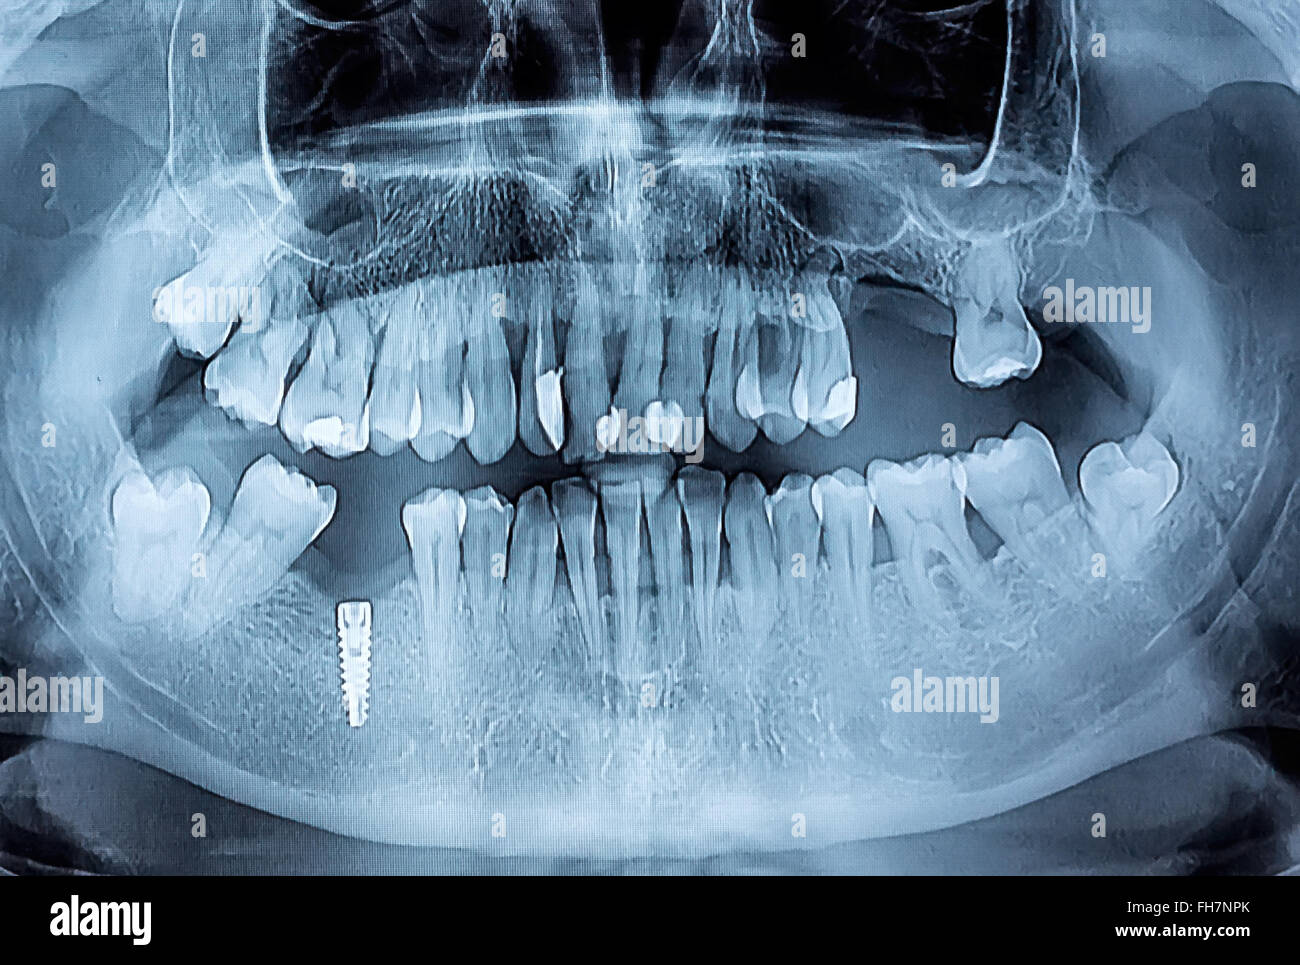

From www.alamy.com

TOOTH DECAY, XRAY Stock Photo 49179032 Alamy Is Teeth X Ray Harmful Your radiation dose for one dental x ray has to be 500 times more than your daily recommended dose in order to cause any harm. Although it is true that a small amount of radiation does go into your body when you get a dental x ray, studies have found that amount is not harmful. You can’t see them, smell. Is Teeth X Ray Harmful.